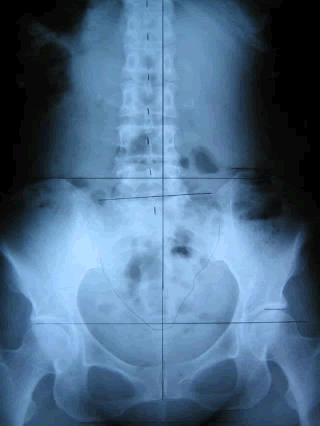

人工的に壊された骨盤

レントゲン Pre&Post(症例)